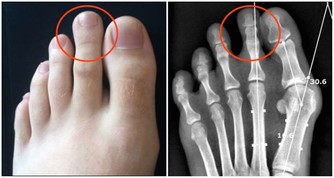

3、肝掌

與常人的手掌顏色大不相同,普通人的手掌顏色紅潤,而患有肝病的病人手掌心泛白無血色。